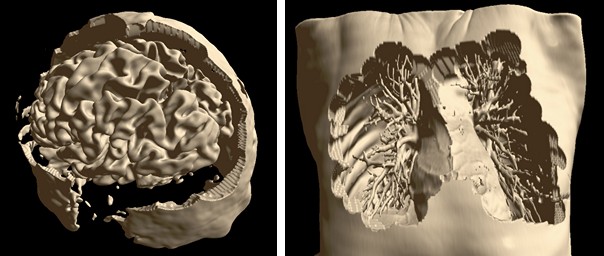

Isosurface Visualization¶

This method suits for bones, skin surface and segmented areas visualization. The base of this method is a search of intersection points between the rays corresponding to pixels and the isosurface. The user selects the level of the isosurface and the clipping plane position with sliders.

Automatic Segmentation¶

Special automatic segmentation methods are implemented for the lungs data and skull tissues separation from brain.